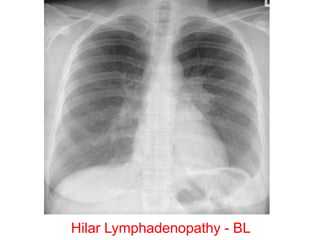

Hilar Lymphadenopathy - BL

Hilar and Mediastinal Lymphadenopathy

Diagnosis?